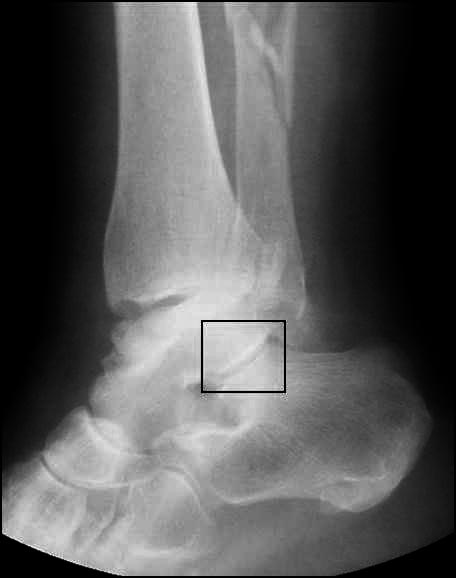

Коллеги! Делюсь первым опытом такой операции Два месяца назад потупил пациент с оскольчатым переломом таранной кости, после ДТП. При поступлении налажено скелетное вытяжение. Ниже рентгенограммы при поступлении

Во вложении всего два примера нормальных взаимоотношений в подтаранном суставе. Постарался подобрать похожие на Вашу проекции. На всех снимках выделена область, где суставные поверхности таранной и пяточной костей всегда должны быть параллельны. В Вашем случае эти линии пересекаются. Подвывих очевиден.

Посмотрите снимки еще раз, пожалуйста . На прямой проекции имеется " ступенька", которая устранена. На боковой проекции до операции имеется диастаз, и винтом дана компрессия. Также удалены осколки из заднего отдела, которые при сращении давали бы проблемы в этом отделе .